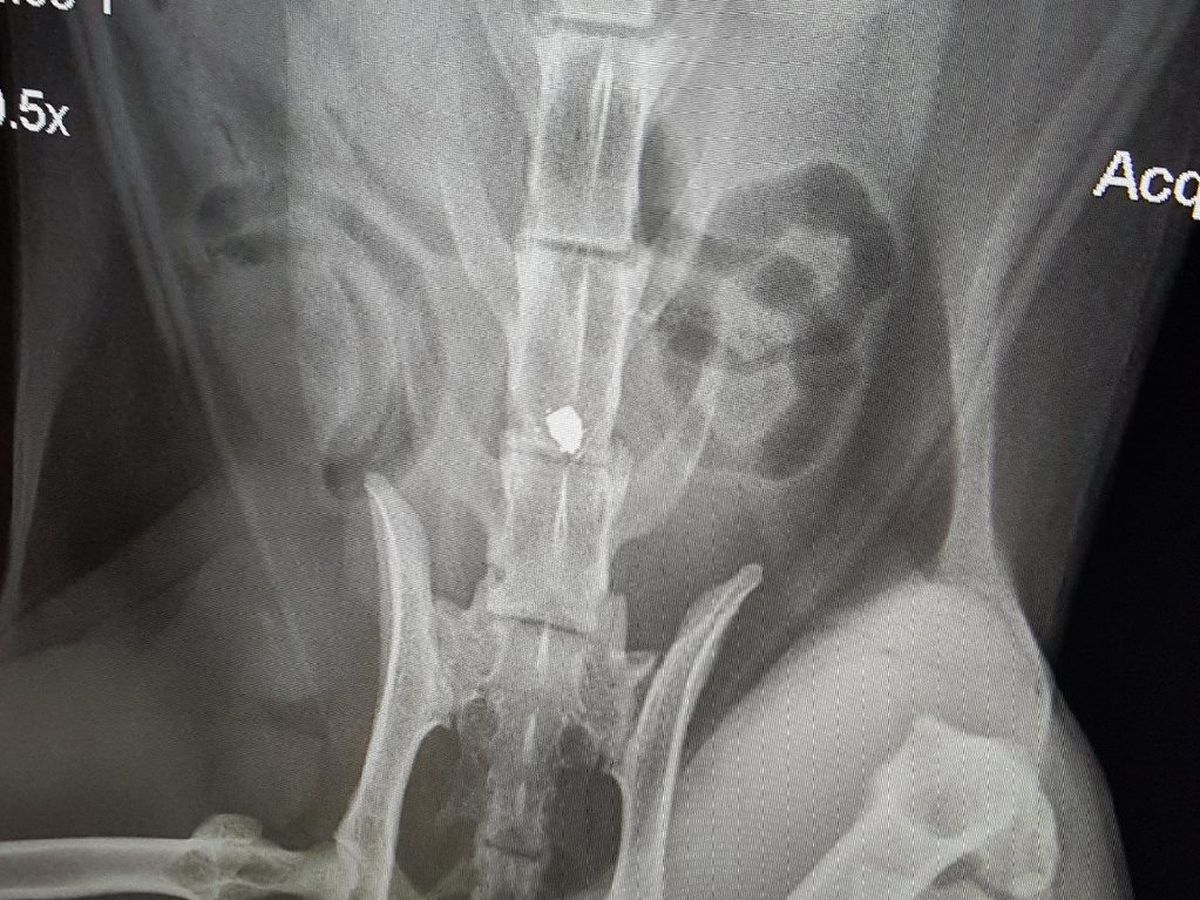

This morning on March 16th, their beautiful, sweet kitties were attacked in Santa Rosa. Carson, the brown striped little guy was shot with a BB gun in his back leaving him paralyzed. Frenchie, the black and white tuxedo kitty had a huge gouge in his foot that was so deep it showed the bone.

They are both at the emergency vet now. Carson's recovery does not look good and the surgery to possibly give him a fighting chance is very expensive. As of right now, he will require to be hand fed and cleaned and will have no use of his lower half. Frenchie will require stitches.